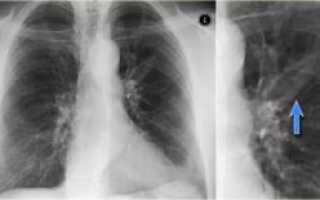

Выявление одиночных очагов в легких. До настоящего времени методом первичного выявления очагов в легочной ткани остается обычное рентгенологическое исследование – рентгенография или флюорография. Одиночные очаги обнаруживаются в 0,2-1,0% всех рентгенологических исследований грудной клетки.

На обзорных рентгенограммах или флюорограммах редко можно выявить одиночный очаг размером 1 см такие контуры служат веским аргументом в пользу злокачественного процесса и, следовательно, показанием для морфологической верификации.

На самом деле, при прохождении флюорографии или рентгенографии сложно выявить ООЛ, размер которого меньше 1 см. Интерпозиция анатомических структур может сделать практически невидимыми и более крупные очаги.

Поэтому большинство врачей советует пациентам отдать предпочтение компьютерной томографии, которая дает возможность рассмотреть ткани в разрезе и под любым углом.

Это полностью устраняет вероятность того, что поражение будет закрыто сердечной тенью, ребрами или корнями легких.

То есть рассмотреть всю картину в целом и без вероятности фатальной ошибки рентгенография и флюорография попросту не может.

- Рентгенография. Простой и быстрый, но не самый информативный метод диагностики. Обычно на снимках можно увидеть только опухоли размером более 1 см;

- Компьютерная томография. Позволяет обнаружить очаги менее 5 мм. Это недоступно для рентгенографии и МРТ;

При проведении рентгенологического исследования, появившиеся в лёгких очаги, выглядят, как овальные затемнения (или же круглые) с резким и реже размытым основанием. Размеры полостей при проведении рентгена могут варьироваться в пределах 5мм. При этом полости могут быть одиночными и множественными.

Очаг Гона на рентгенограмме выглядит как затемненное образование с резкими очертаниями. Излюбленным местом локализации признаются нижние и средние зоны органа. Легочный рисунок при этом редко изменен, корень практически не расширен.